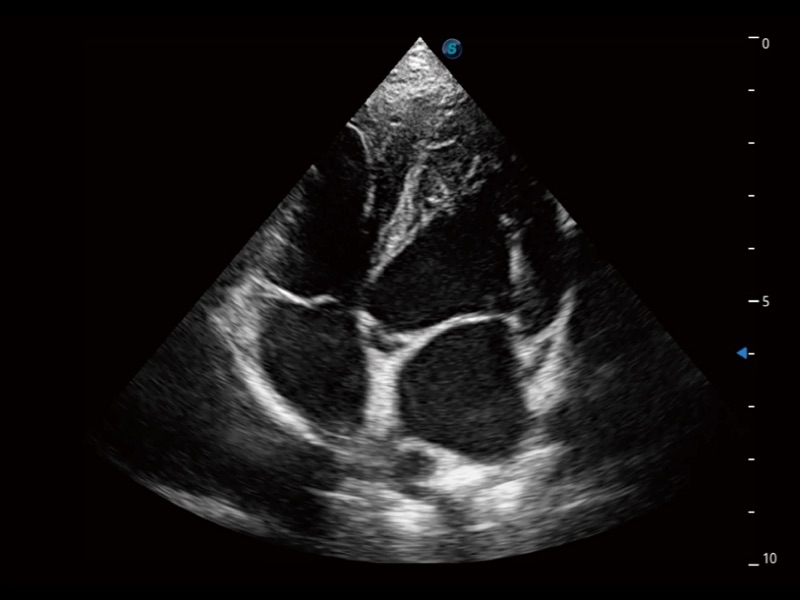

(犬)四腔心